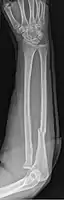

Fractures of the ulna can occur at different levels of the bone: near the wrist, in the middle or near the elbow.[2] The fracture may be confined to the ulna or accompanied with damage to the radius or the wrist or elbow joints.[2]

- Galeazzi fracture - not a fracture of the ulna but a displaced fracture of the radius accompanied by a dislocation of the ulna at the wrist, where the radius and ulna come together.[2]

Galeazzi facture (displaced fracture of the radius)